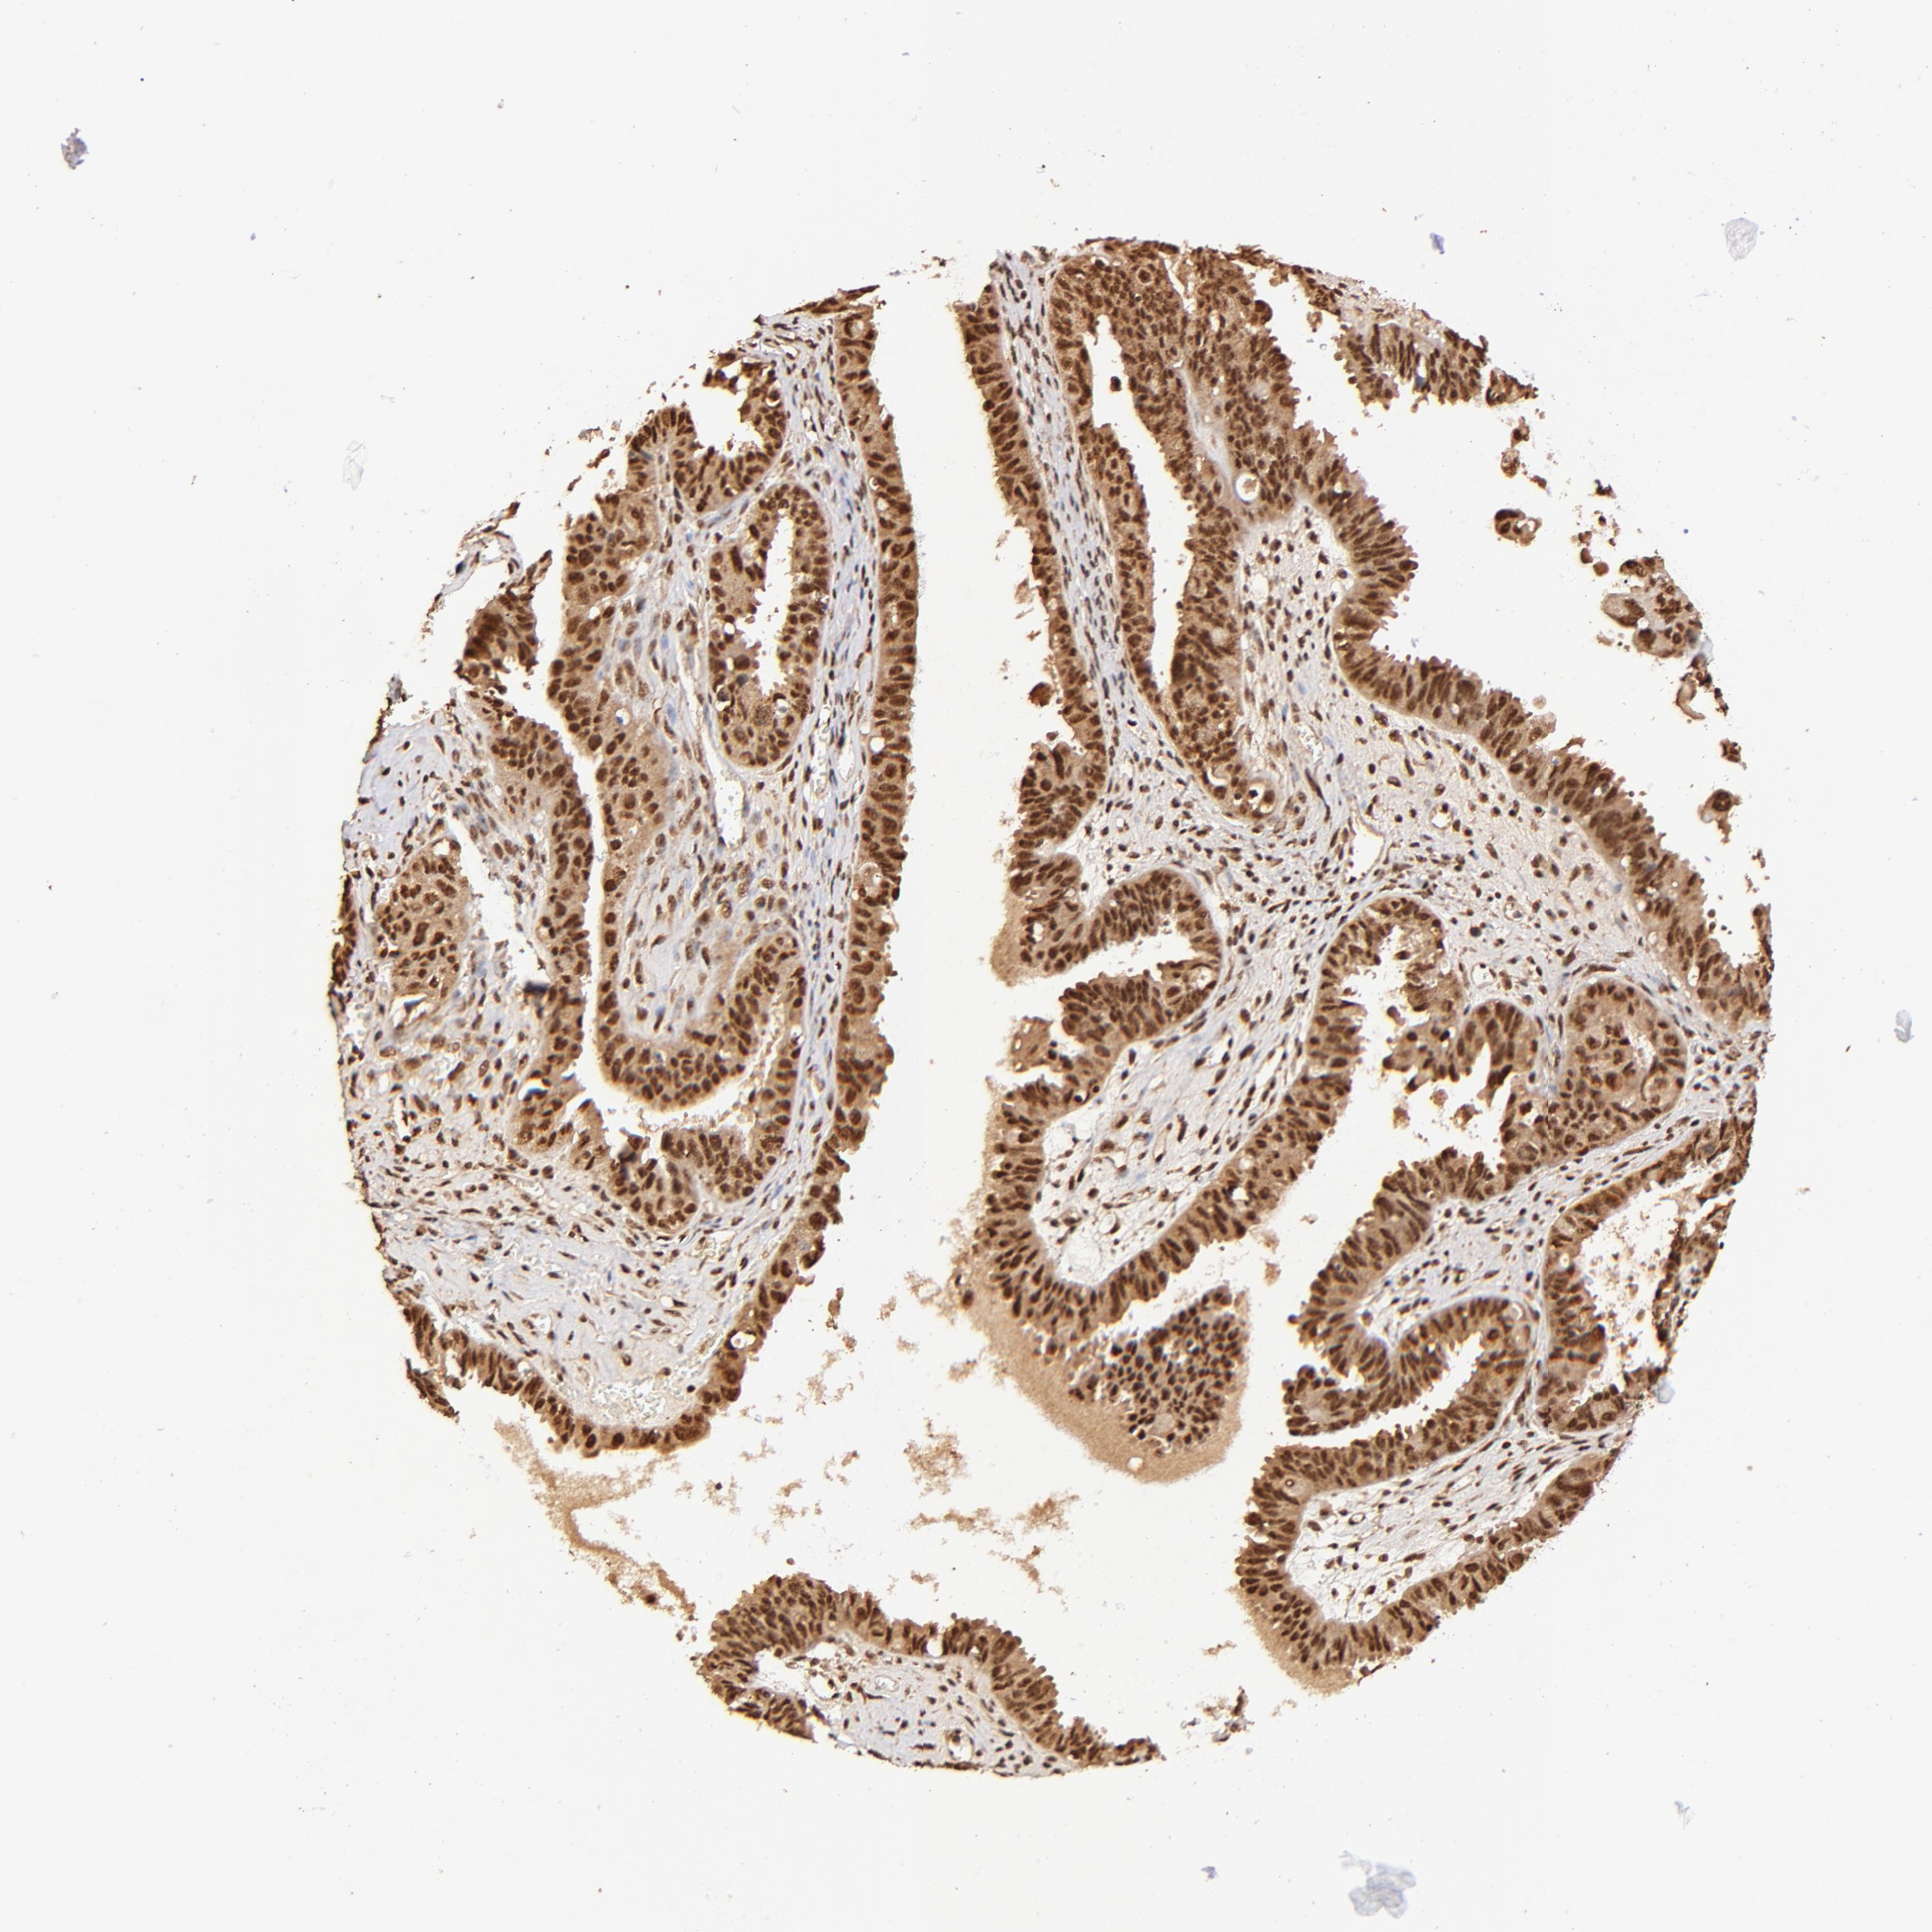

OVARIAN CANCER - Protein expressioni

A mouse-over function shows sample information and annotation data. Click on an image to view it in a full screen mode. Samples can be filtered based on level of antibody staining by selecting one or several of the following categories: high, medium, low and not detected. The assay and annotation is described here.

Note that samples used for immunohistochemistry by the Human Protein Atlas do not correspond to samples in the TCGA dataset.

Antibody stainingi

Antibody staining in the annotated cell types in the current human tissue is reported as not detected, low, medium, or high, based on conventional immunohistochemistry profiling in selected tissues. This score is based on the combination of the staining intensity and fraction of stained cells.

Each image is clickable and will lead to virtual microscopy that enables deeper exploration of all samples and also displays staining intensity scores, fraction scores and subcellular localization as well as patient and tissue information for each sample.

Antibody HPA003184

Antibody HPA003185

Cystadenocarcinoma, mucinous, NOS

Carcinoma, endometroid

Cystadenocarcinoma, serous, NOS